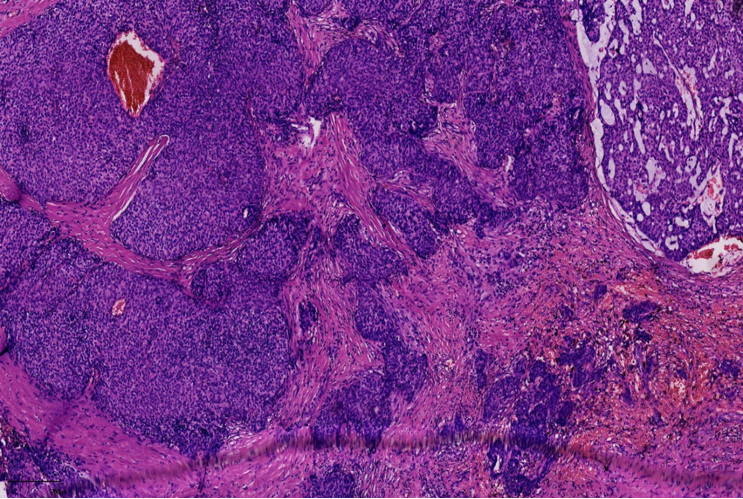

1、浸润性实性乳头状癌:保留实性乳头状结构,体积大的团巢,轮廓不规则,间质促纤维反应,肌上皮缺失,原位SPC背景

浸润性SPC

原位SPC的乳头轴心及导管周边的肌上皮可以存在,也可以不同程度减少。原位SPC可被视为导管原位癌的特殊亚型,因此,临床可以按导管原位癌处理。极端状态下,导管周边的肌上皮可以完全缺失,此时可被称为膨胀性或推挤性浸润,其形态与原位SPC高度相似。研究显示,膨胀性浸润的SPC通常不发生转移,因此仍可按导管原位癌处理。

当在原位SPC的背景上,部分原位SPC轮廓变得不规则,或呈地图、锯齿状,并出现促纤维反应,或浸润脂肪,可称为原位SPC伴浸润(毁损性浸润),这时需按浸润癌处理。